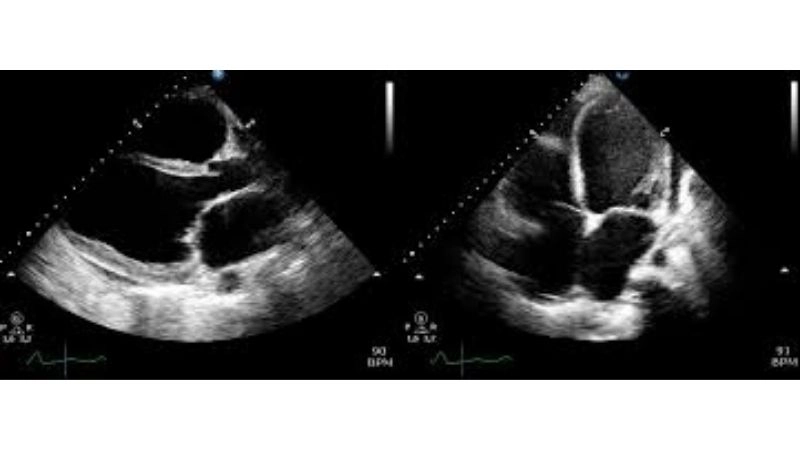

Images visual examples of Peripartum (Postpartum) Cardiomyopathy

Visual examples of Peripartum (Postpartum) Cardiomyopathy often show an enlarged heart with weakened walls, highlighting reduced pumping ability and fluid buildup in the lungs and surrounding tissues.